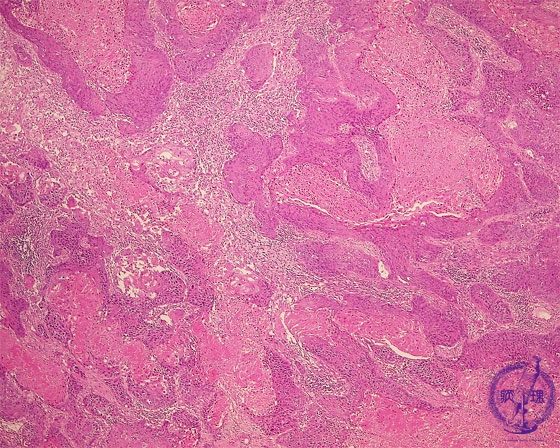

- ★(17)Non-small cell lung carcinoma(squamous cell carcinoma)

Microscopic view (HE stain, low power view): Squamous cell carcinoma proliferates in an irregular geographic (map-like) pattern. Keratinocyte necrosis is prominent (arrow). Unlike in adenocarcinoma well-formed tubules are not seen.